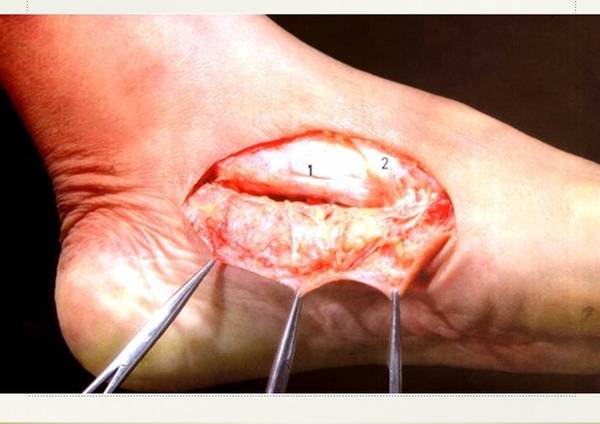

今天讲课

查了些文献

对足内侧皮瓣进行了回顾总结